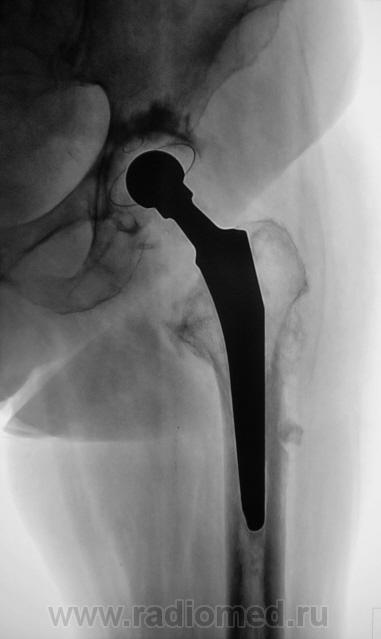

Шарнирный эндопротез. Пластиковая чашка установлена (по-моему правильно) в очищенной от суставного хряща вертлужной впадине и зафиксирована при помощи костного цемента. Ножка протеза в порядке. Какие-то остеофиты на латеральном контуре бедра (мелко: плохо видно).